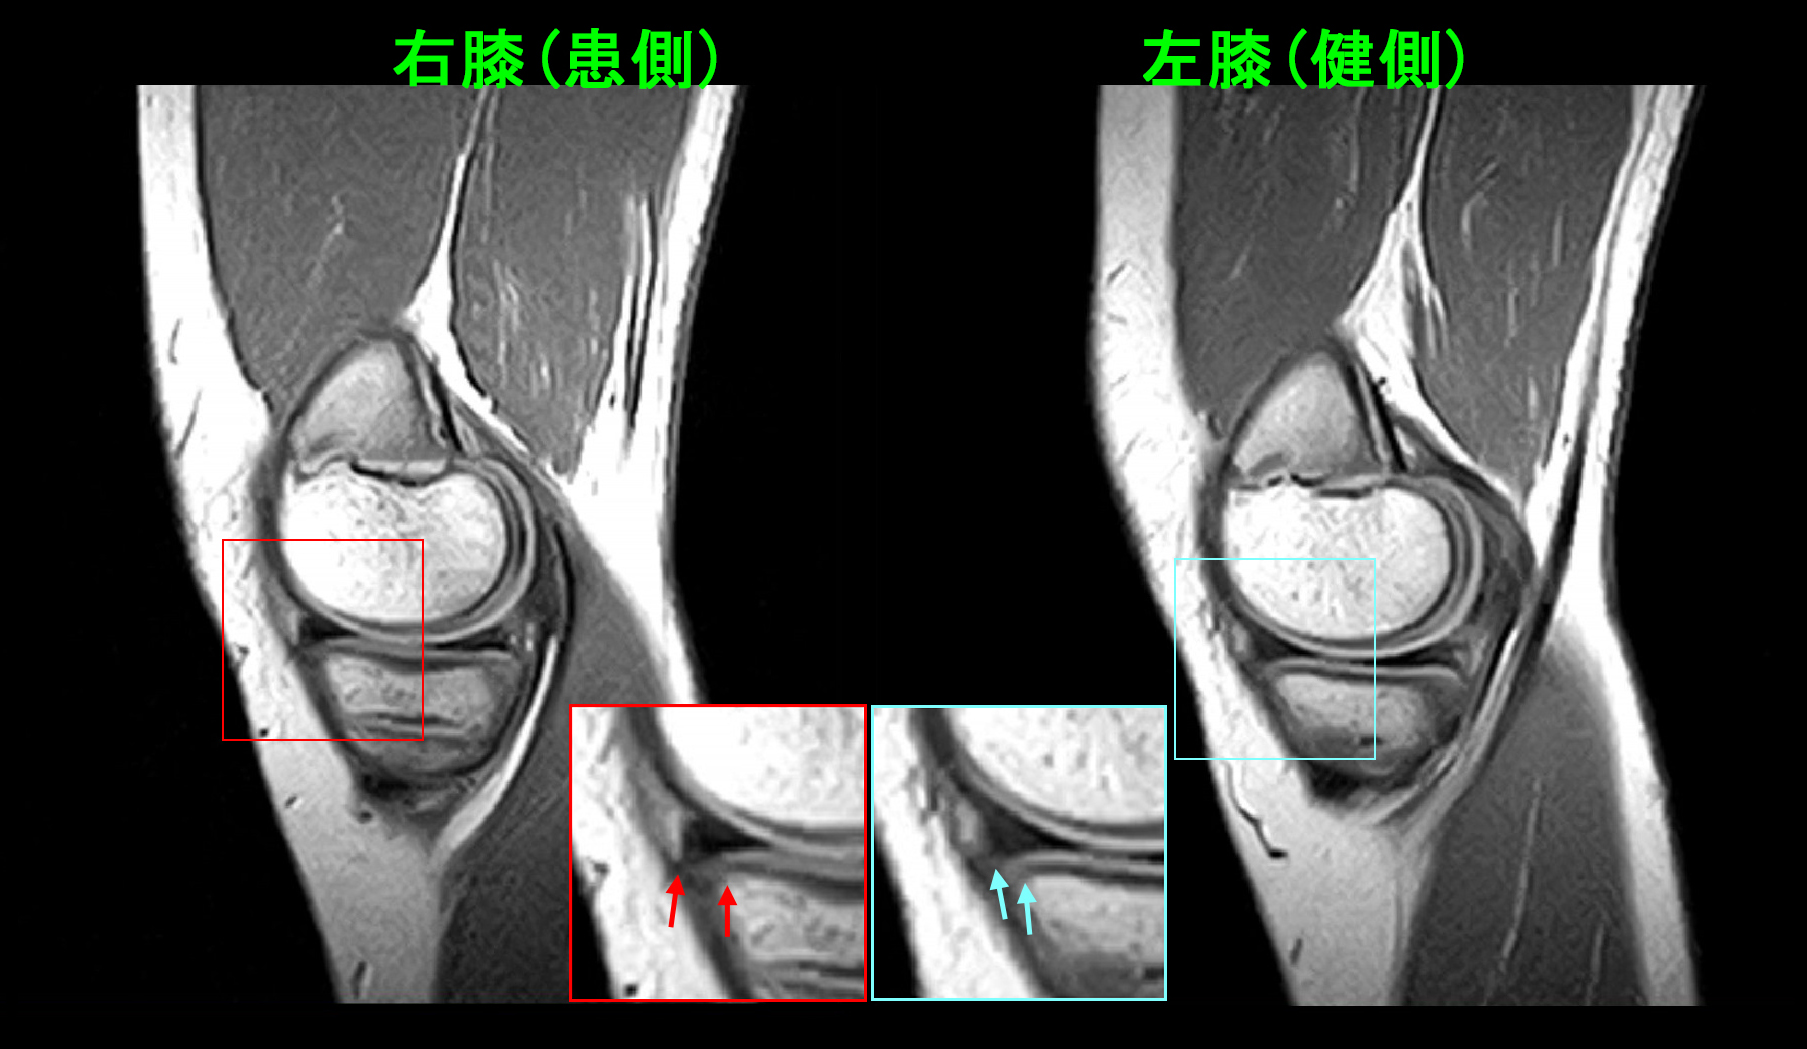

18才女 Xp.jpg

18才の高校3年生の女子生徒です。令和7年9月6日自転車での学校帰りに同じ方向に走っていた車が左折してきて、それを避けようとして左側に転倒し、左膝を打撲しました。9月7日他整形外科受診して、打撲の診断でシップと投薬を受け、服薬は有効だったそうですが、服薬終了で左膝痛は再発したそうです。以後時々左膝痛があり、10月12日さらに症状は悪化し、左膝屈曲で痛み、椅座位でも痛みがあるということで、10月25日に当院を受診されました。しかし、卓球での痛みはVAS4というので大したことないという印象でした。理学所見(診察のでの所見)で、左脛骨内顆部に圧痛(押すと痛いという所見)を認めるため(赤矢印)脛骨の骨損傷も疑われMR検査を勧めました。